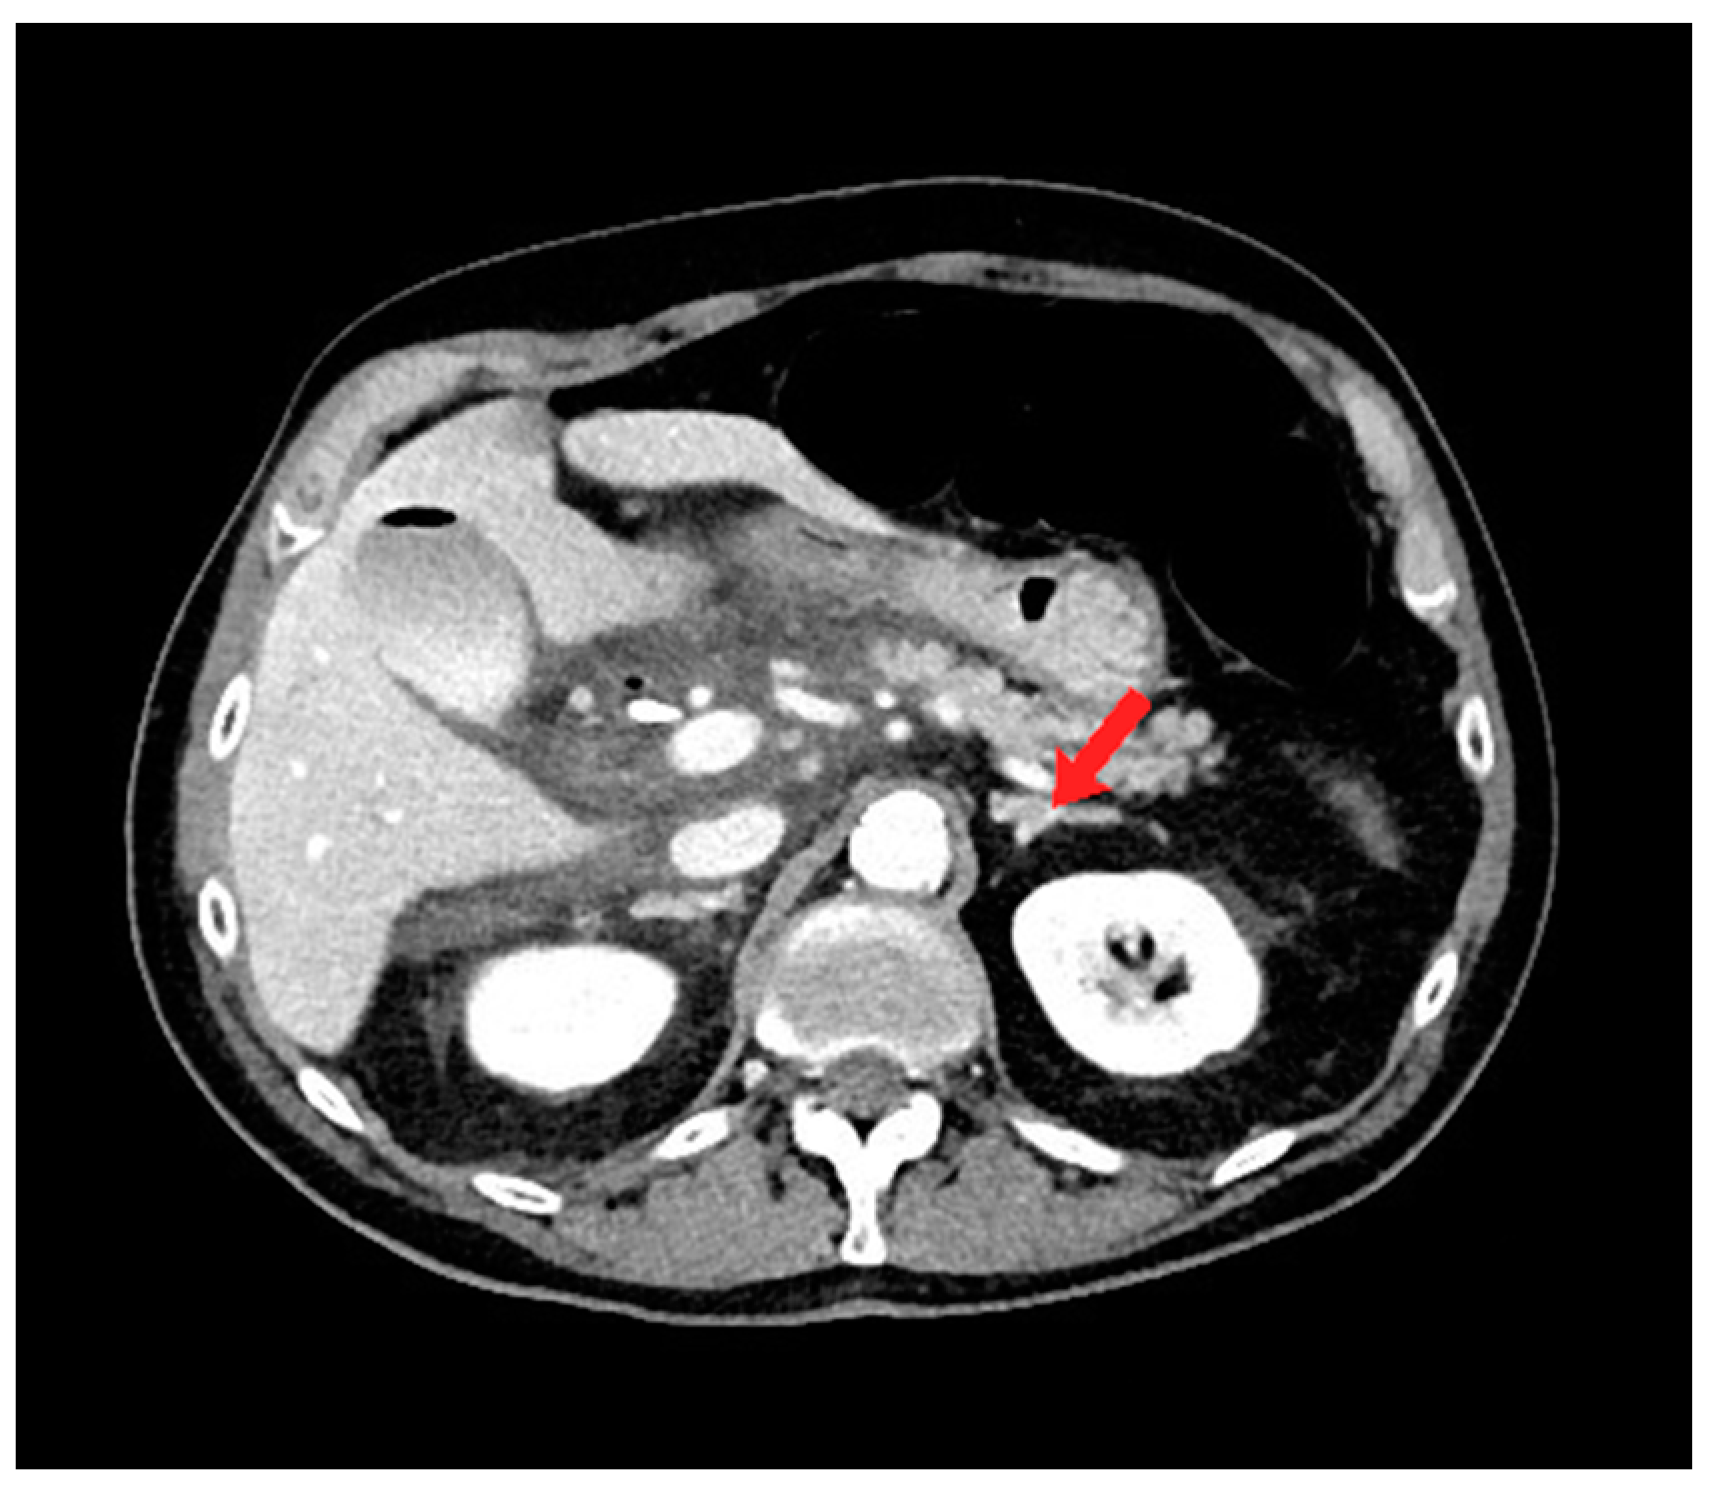

A 73-year-old male with a past medical history of ampullary neoplasm status post endoscopic ultrasound with fine needle aspiration and plastic biliary stent placement presents with right upper quadrant (RUQ) pain, elevated bilirubin, and leukocytosis two days after receiving endoscopic retrograde cholangiopancreatography (ERCP). Computed tomography (CT) of the abdomen revealed moderate free fluid adjacent to the extrahepatic biliary system, pancreatic head, and proximal duodenum (Figure 1). Blood cultures were negative. Repeat ERCP was performed, which showed biliary stent obstruction. The stent was removed and replaced with a 10 mm × 40 mm bare metal stent. Three days after the repeat ERCP, the patient reported worsening abdominal pain and CT showed an increase in RUQ simple fluid. A hepatobiliary iminodiacetic acid (HIDA) scan was performed to rule out biliary leak, which was negative. Due to the patient’s worsening leukocytosis, a repeat CT was performed which showed interval increase, organization, and hyperenhancement of a periduodenal collection. The patient therefore underwent CT-guided drainage of the collection with moderate sedation, which ultimately grew yeast (Figure 2a).

Figure 1.

Axial computed tomography (CT) image shows moderate free fluid adjacent to the extrahepatic biliary system, pancreatic head, and proximal duodenum. Note the normal appearance of the left adrenal gland (red arrow).